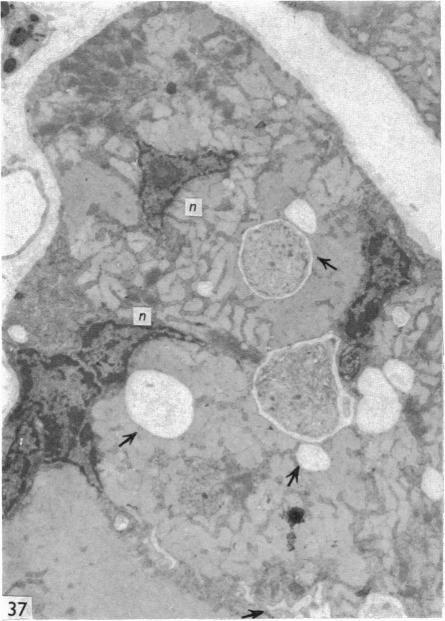

Re-innervated extensor digitorum longus, soleus and plantaris muscles of the rat were studied after denervation performed at various postnatal ages. The muscle fibres, which normally run from tendon to tendon as independent units, were found to be very frequently connected by myomuscular junctions, both in the form of terminal insertions of one fibre into another and of lateral bridges which may join two or more muscle fibres at one or more levels. Positive reaction for AChE activity was demonstrated at the level of the junctions. Incubation for myosin ATPase activity showed that myomuscular junctions are only found between fibres of the same histochemical type, which in re-innervated muscles are usually aggregated in 'type groupings'. Ultrastructural features were similar in both forms of myomuscular junctions. The appearance is that of an interdigitation of muscle projections from neighbouring fibres, each projection being covered by a basement membrane with attached collagen fibrils. The finger-like projections at their endings contain vesicles and elongated cisternae filled with granular dense material. It is postulated that the synchronous activity of neighbouring fibres within the compact motor units of reinnervated muscles is a causal factor initiating the formation of myomuscular junctions.

在不同出生后年龄进行去神经支配后,对大鼠重新神经支配的趾长伸肌、比目鱼肌和跖肌进行了研究。通常作为独立单元从肌腱延伸至肌腱的肌纤维,被发现经常通过肌-肌连接相连,其形式既有一根纤维末端插入另一根纤维,也有横向桥接,横向桥接可在一个或多个水平连接两根或更多肌纤维。在连接部位检测到乙酰胆碱酯酶(AChE)活性呈阳性反应。肌球蛋白ATP酶活性孵育显示,肌-肌连接仅在相同组织化学类型的纤维之间发现,在重新神经支配的肌肉中,这些纤维通常聚集形成“类型分组”。两种形式的肌-肌连接的超微结构特征相似。外观呈现为相邻纤维的肌肉突起相互交错,每个突起被带有附着胶原纤维的基底膜覆盖。指状突起的末端含有囊泡和充满颗粒状致密物质的伸长池。据推测,重新神经支配肌肉的紧密运动单位内相邻纤维的同步活动是引发肌-肌连接形成的一个因果因素。